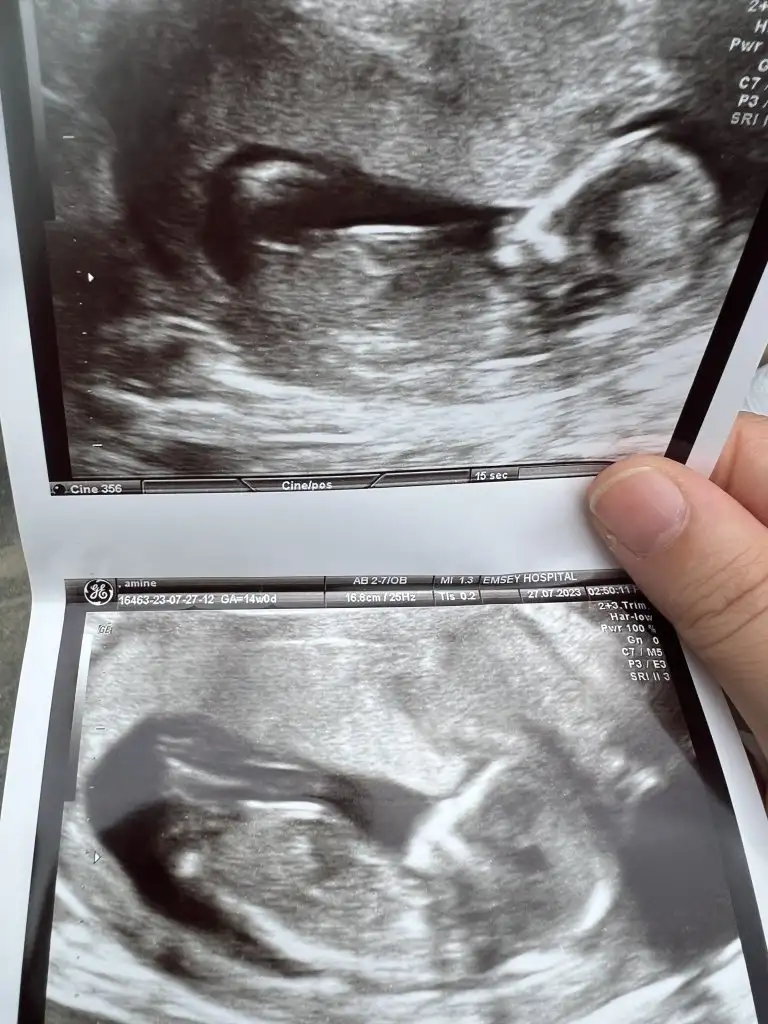

Merhaba ben kadın doğumda ikili taramaya girdim.Kendi kadın doğum doktorum söyledi cinsiyet tahminini detaylı ultrasondaBizde şimdi ikili tarama için geldik hayırlısıyla güzel sonuçlarla atlatırız inşallah cinsiyet tahminini kim söyledi acaba?ikili tarama için radyolojiden randevu aldık biz ondan soruyorum

Bende haftaya cuma tekrar gidiyorum ikili test için 45 mm olması lazımmış benim 39 mm dediCinsiyetler belli olmaya başlamışçatlıyorum ya daha haftaya perşembe gideriz biz ikili için of

Maşallah bı şey dicem ikili testi yapmak için aç mi tok mu gittiniz kan falan verildi miBenimde dun ikili testim yapildi iki ayri doktorda randevumvardi ikiside erkek dedi12. Haftamdayım